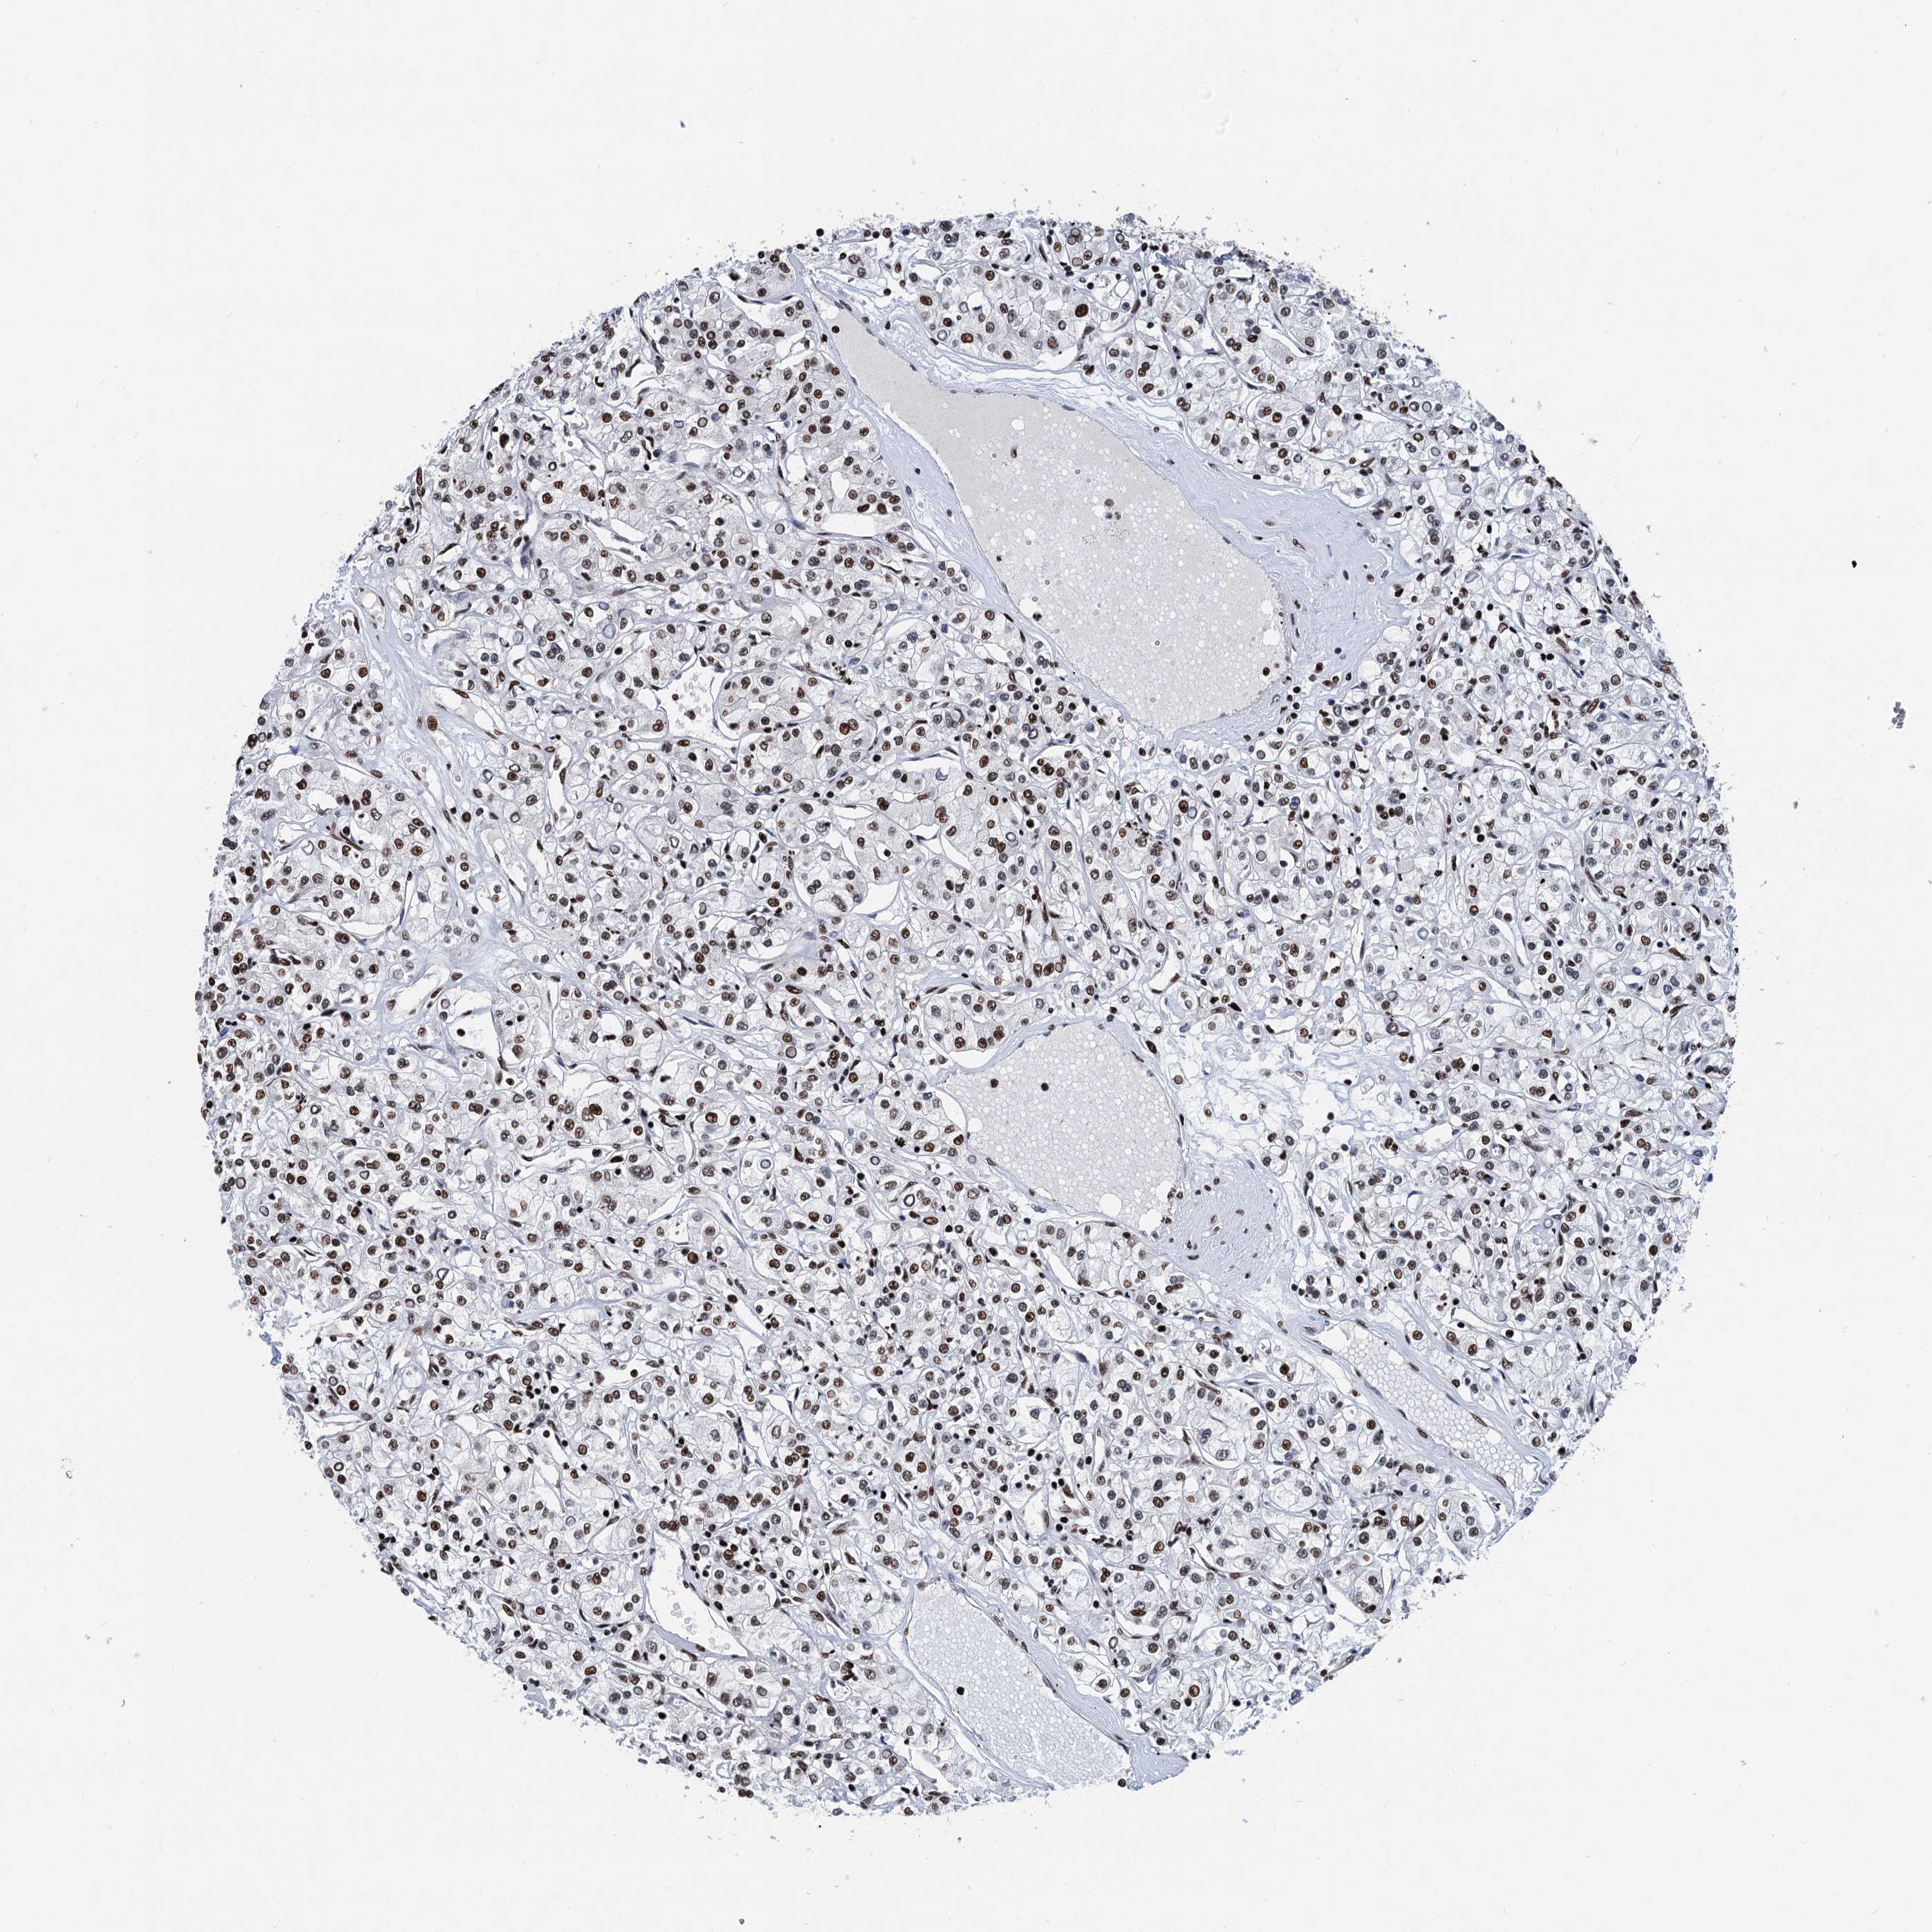

CANCER RENAL CANCER Show tissue menu